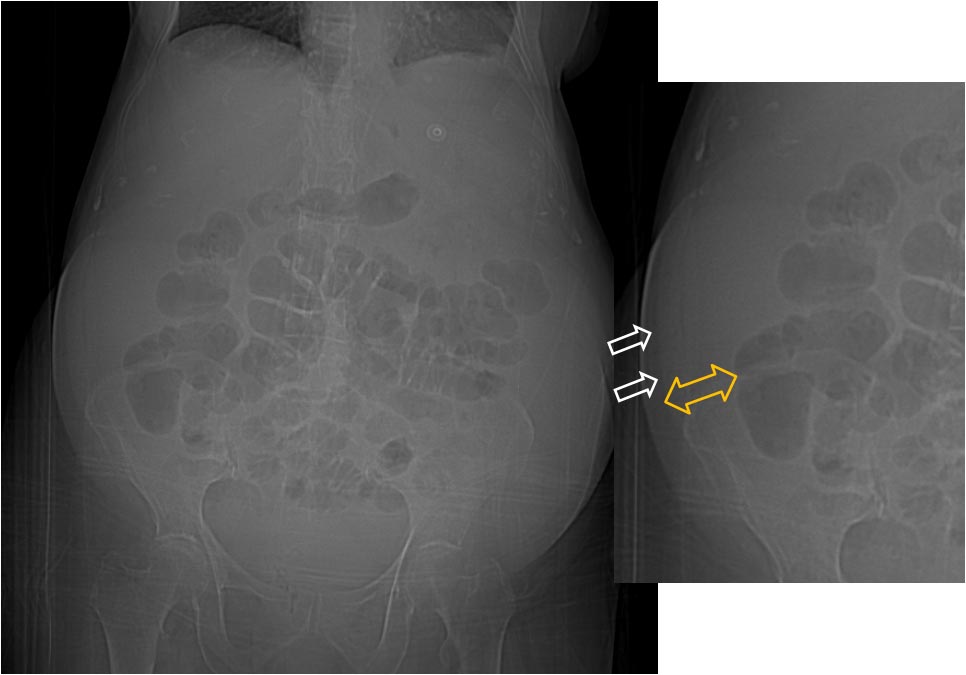

Normalmente en la radiografía simple de abdomen vemos una banda vertical poco densa (grasa del flanco) entre el colon ascendente o descendente y la pared abdominal. Cuando existe hemoperitoneo o ascitis, el líquido se introduce en este espacio, ensanchándolo y oscureciendo las haustras del colon y la línea peritoneal. En la imagen ampliada vemos la banda grasa del flanco estrechada y un aumento de la distancia desde esta línea hasta el colon.

Radiografía de abdomen normal que muestra las líneas grasas de los flancos (flechas).

A la izquierda, corte de TC de abdomen con contraste oral e intravenoso que muestra abundante líquido ascítico, especialmente acumulado en los flancos. Obsérvese como el líquido (flecha naranja) desplaza medialmente el colon (flecha verde). A la derecha, un estudio normal para comparar.